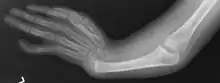

Radial Ray Malformations

This is characterized by hand and arm abnormalities. The following are specific characteristics:

- Malformed or absent (aplasia) thumb

- A thumb that looks more like a finger

- Partial or complete absence of a radius

- Shortening and radial deviation of the forearms

- Triphalangeal thumb

- Duplication of the thumb (preaxial polydactyly)